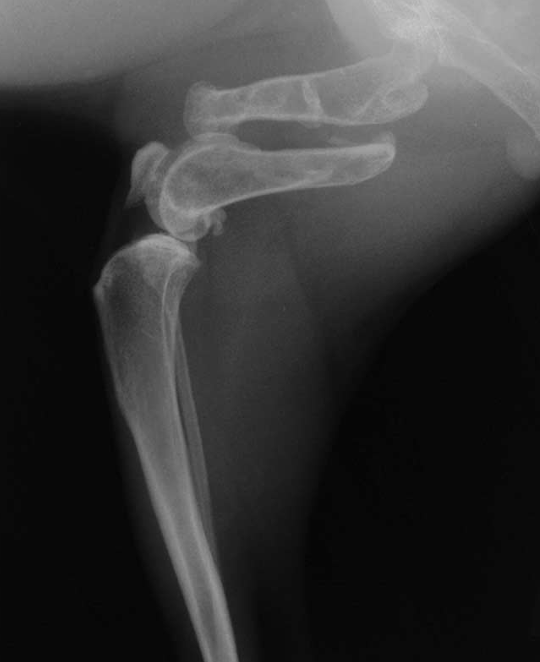

What is shown in this radiograph?

widening of humero-ulnar joint and secondary UAP due to premature distal ulnar physis closure